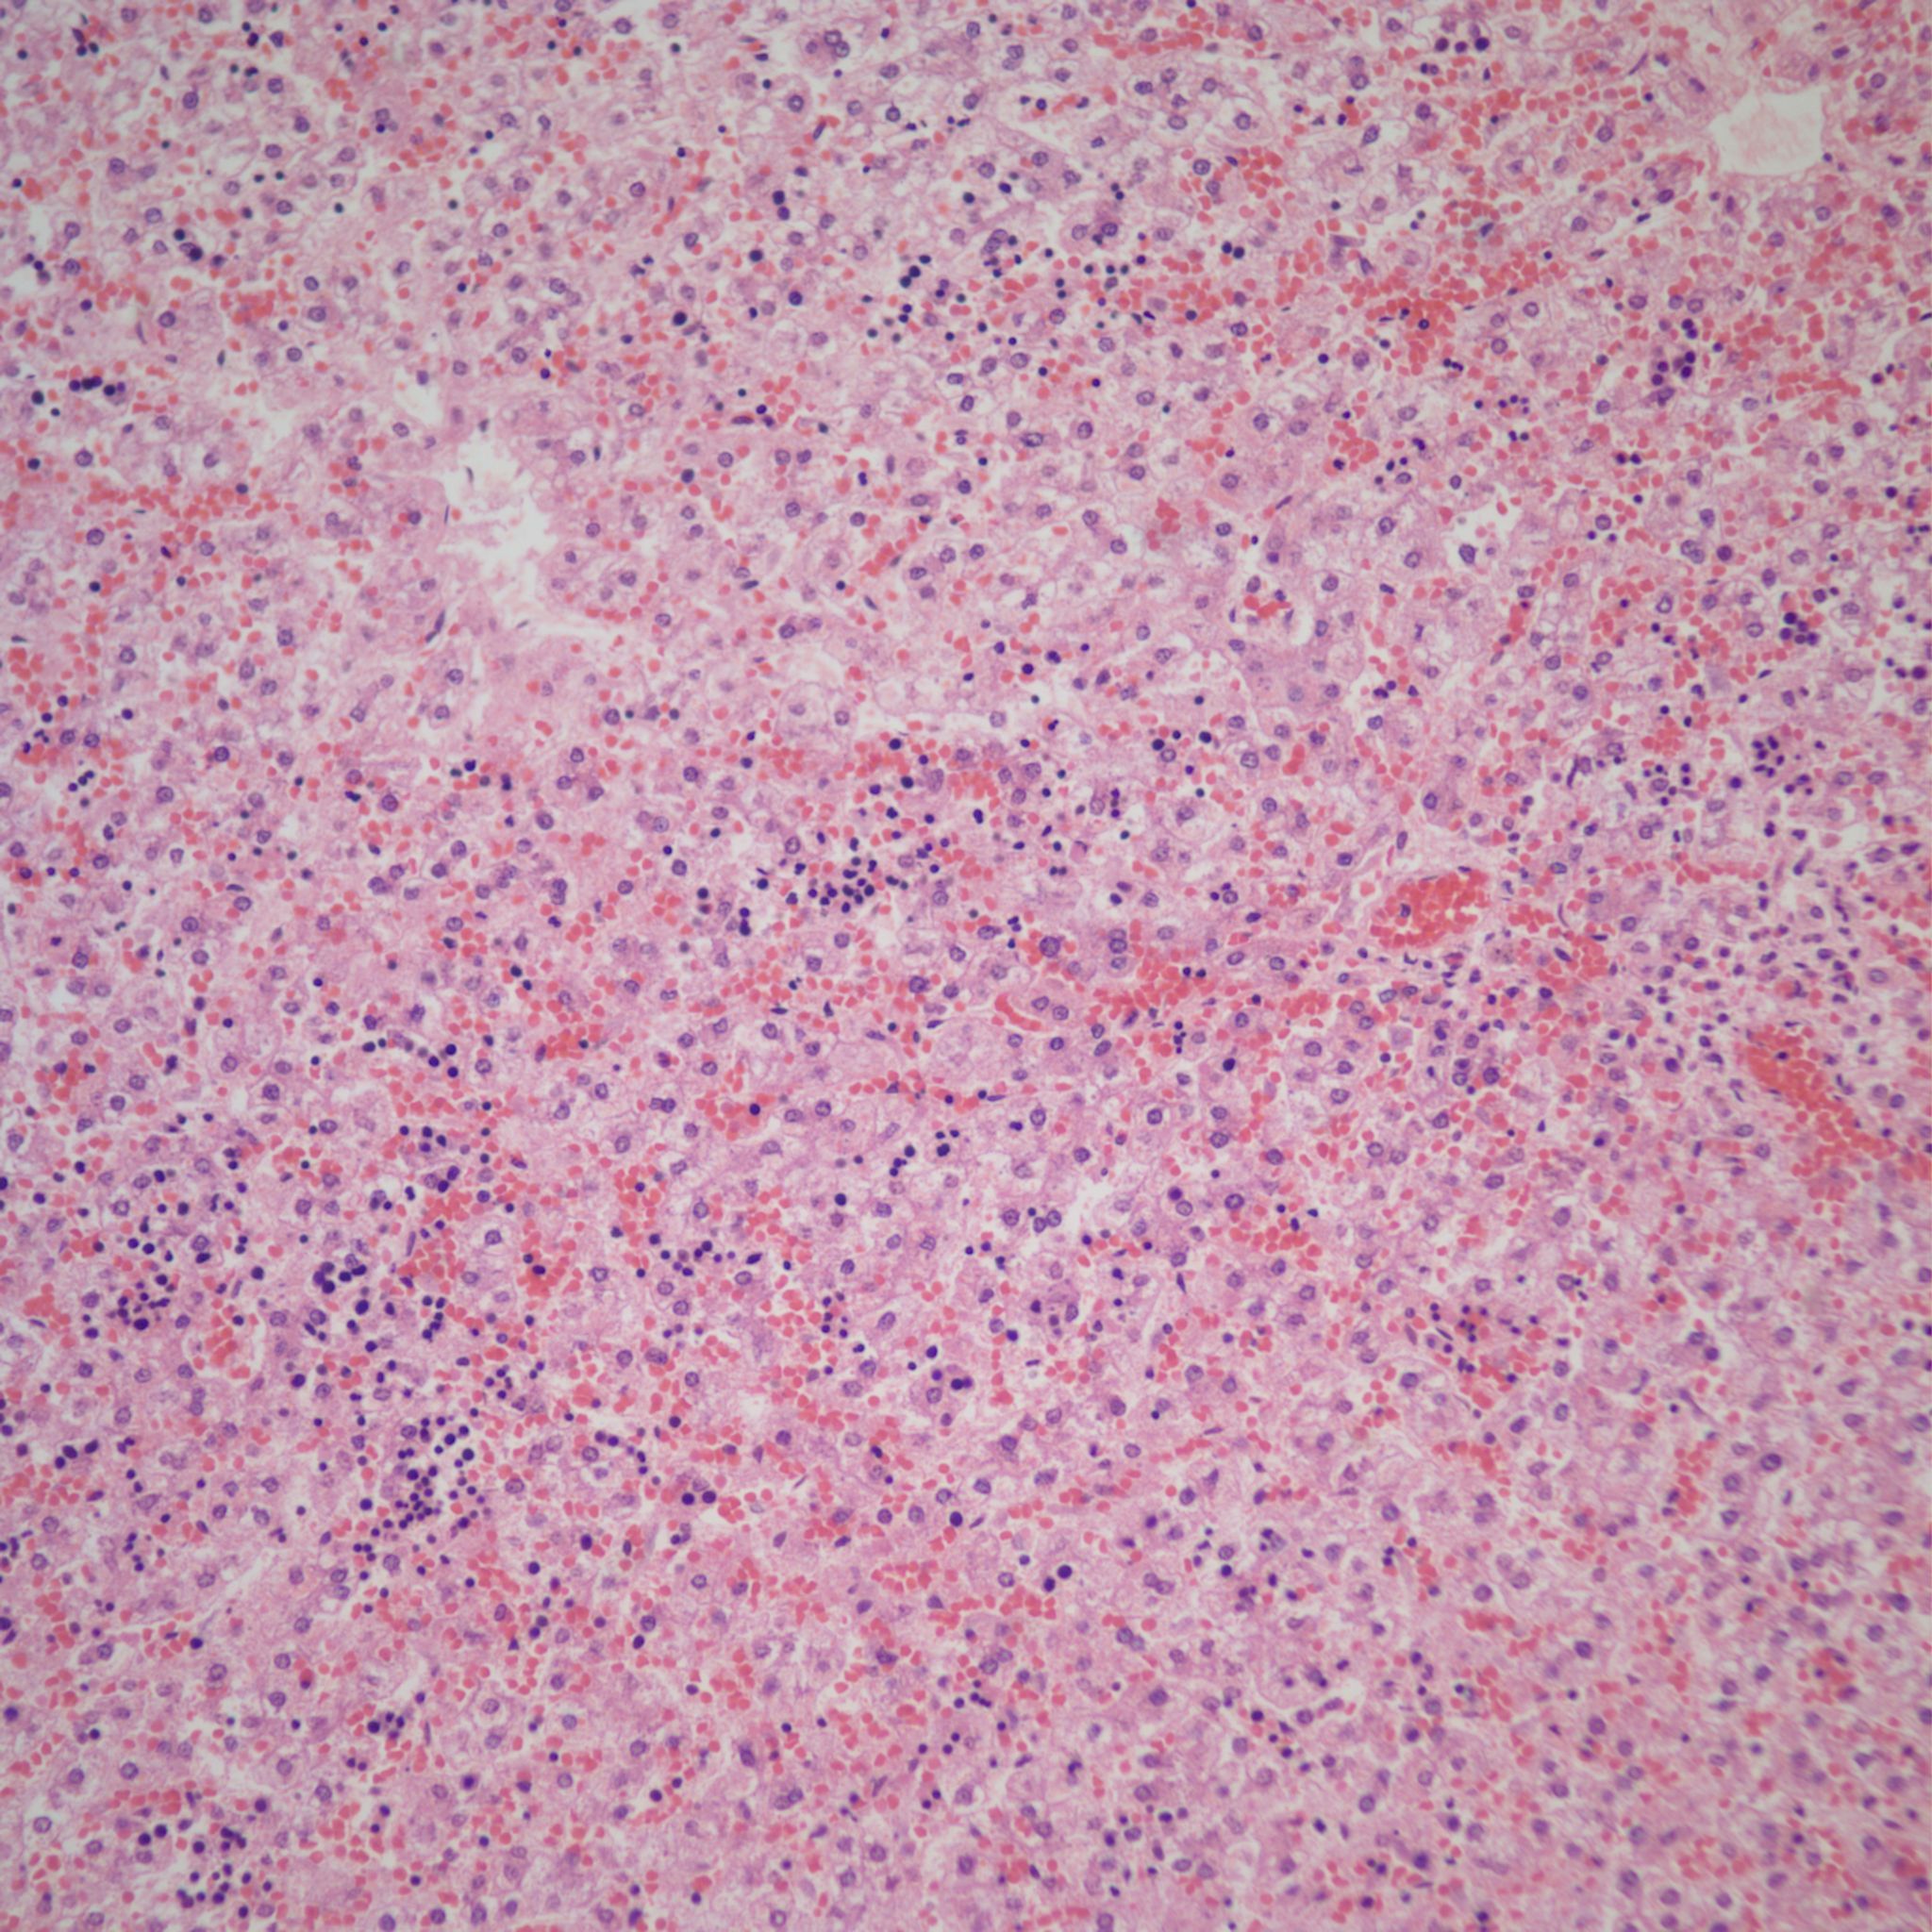

Hemorrhage and congestion: In the fetal liver, the majority of the oxygenated blood from the umbilical vein is supplied to the portal venous system but with a large portion also shunted through the ductus venosus to the inferior vena cava. With fetal hypoxia, the ductus venosus widens and more blood is shunted to the heart8. Despite this shift, in some stillbirths with fetal asphyxia, the liver shows marked sinusoidal congestion likely from a sudden increase in right heart pressure from cardiac hypoxia and poor contraction (Fig 10a, b).

Constriction of the ductus arteriosus would also be expected to suddenly increase right heart pressure and liver congestion. The sinusoidal congestion may be accompanied by periportal hemorrhage likely because the increase in right atrial pressure is also transmitted to the portal system through the ductus venosus (Fig 11).